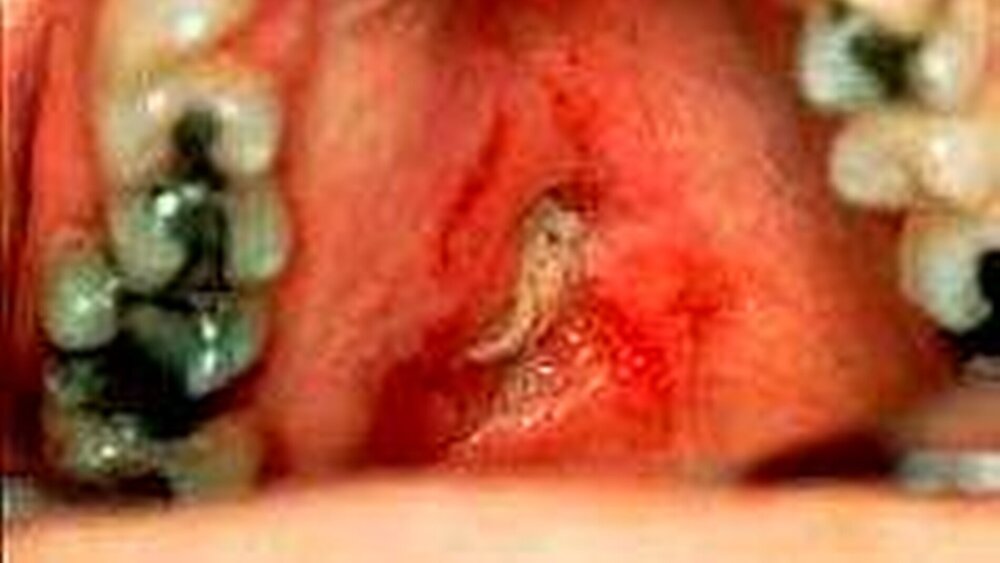

Der Begriff „Tumor“ wird in der allgemeinen Pathologie als neu aufgetretene Volumenzunahme (Schwellung) einer Region aufgefasst. Er wird dabei gleichermaßen für Neoplasien (Abbildung 2) als auch für entzündungsbedingte Schwellungen (Abbildung 3) verwendet, da der „Tumor“ eines der fünf klassischen Entzündungszeichen darstellt. Neben diesen beiden großen Erkrankungsentitäten gibt es jedoch verschiedene andere Erkrankungen, die zu intraoralen Schwellungszuständen führen können und deren Kenntnis in der Differentialdiagnostik von großer Bedeutung ist. Tabelle 2 gibt dabei einen Überblick über die verschiedenen pathologisch definierten Erkrankungen, die der Zahnarzt in seine differentialdiagnostischen Überlegungen einfließen lassen sollte.

Sollte nach Ausschöpfen der verschiedenen diagnostischen Maßnahmen noch Unklarheit über die zu Grunde liegende Erkrankung bestehen oder liegt ein malignomsuspekter Befund vor, so stellt die Gewinnung einer Gewebeprobe den entscheidenden Schritt zur definitiven Diagnostik dar (Abbildung 7).

Während Gewebeproben von in der Tiefe liegenden Prozessen grundsätzlich auch durch Feinnadelbiopsien gewonnen werden können, stellt insbesondere im intraoralen Bereich die Probeexzision das klinische Verfahren zur Gewebegewinnung dar. Die meisten Erkrankungen lassen sich nach konventioneller Aufarbeitung dann pathohistologisch determinieren, während in Einzelfällen histologische Spezialuntersuchungen notwendig werden.